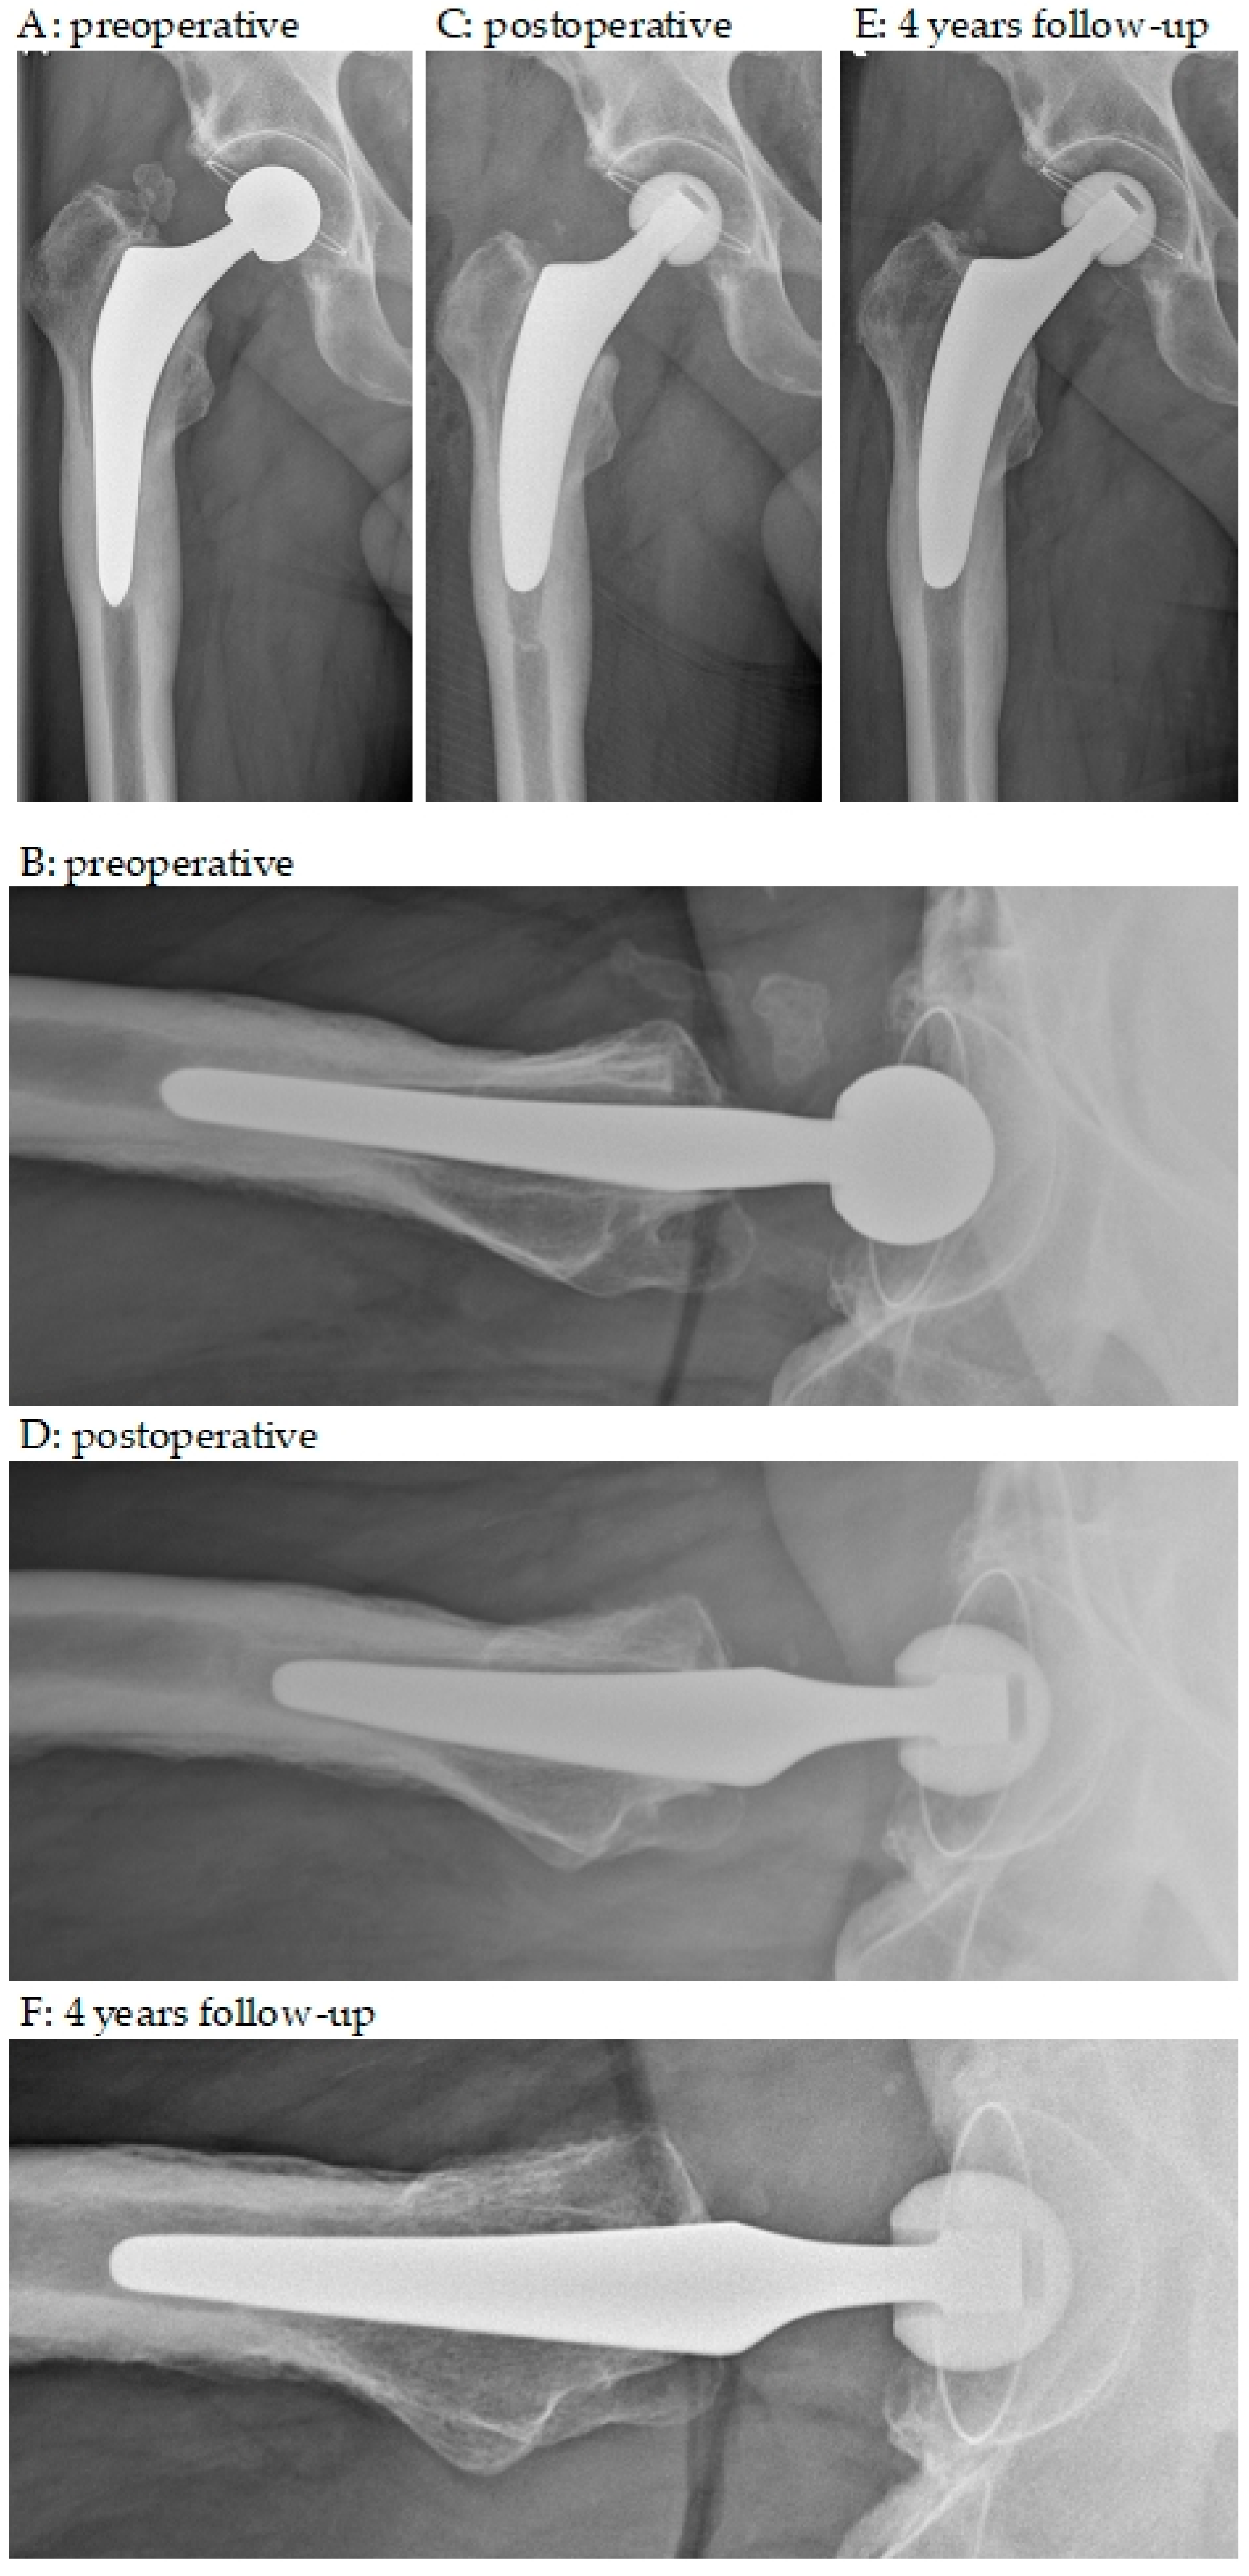

3.2. Radiographic Outcomes